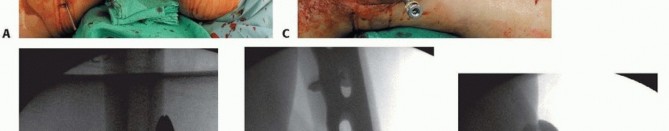

### FIG 9 • Critically ill elderly polytrauma Jehovah's witness patient with left C1 distal femur fracture. A,B. Initial injury AP and lateral views. C,D. Due to extremely low hematocrit, external fixation was the only surgical option allowed to minimize blood loss. Radiographs in bridging external fixation. The AP shows excellent alignment but the lateral shows the expected extension deformity secondary to pull of gastrocsoleus complex. E,F. After 5 weeks in an external fixator, AP and lateral radiographs show callus formation (red arrows). Patient is now cleared for definitive surgical intervention. Antegrade intramedullary nailing has been described and can be used for distal fractures with a large enough distal segment to allow for two locking screws. Malalignment has been a problem, as has adequate fixation. 4, 8 Retrograde intramedullary nailing can be used in the following cases ( FIG 10): All extra-articular type A fractures greater than 4 cm from the joint. This minimal length of the distal femur allows for multiplanar interlocking in the distal fragment. Type C1 or C2 fractures where the articular fracture can be anatomically reduced closed or with limited exposure. Percutaneous screws are used for the articular injury. Periprosthetic fractures around a total knee arthroplasty with an “open box” femoral component Most surgeons prefer to use a long nail, but short supracondylar nails are available as well. Multiple-hole short supracondylar nails have fallen out of favor. Plate fixation ORIF with plates can be used for all types A and C fractures but is ideal for the following injuries: Very distal type A fractures within 4 cm of the knee joint All articular type C fractures, but always for C3 types Periprosthetic fractures about a “closed box” femoral component of a total knee arthroplasty The partial articular type B1 or B2 if an antiglide plate is needed Plate options (preferred to least preferred; fixed-angle devices preferred) Fixed-angle locking plates (percutaneous jigs are advantageous and allow for minimally invasive techniques) Variable-angle (polyaxial) locking plates—allow for “fixed variable locking” within a defined range. It is useful for distal fractures and allows for increased screw 473 trajectories to gain additional locked fixation in short segments, which may not be feasible with fixed-angle trajectory plates ( FIG 11).

### FIG 10 • A,B. AP and lateral radiographs of an elderly patient with multiple comorbidities with an extra-articular distal femur fracture (AO type A; an incomplete intercondylar split— red dashed arrow). C,D. Postoperative radiographs showing stabilization with retrograde intramedullary nail. E,F. One-year postoperative radiographs showing a healed fracture with some subsidence of the metaphyseal region and mild protrusion of hardware through the notch. Ninety-five-degree condylar screw Ninety-five-degree blade plate Nonlocking plates with or without medial support (medial plate or external fixation) Limited internal fixation Limited fixation with screws only can be used for partial articular type B, especially type B3. The amount of open reduction required depends on the adequacy of closed reduction techniques and obtaining an anatomic reduction of the joint surface. Headless screws are useful for type B3 fractures in which the screws have to penetrate the joint surface ( FIG 12). Countersinking the screw heads can also be performed. Biomechanics of fixation: implant considerations There has been concern that the newer locking plate constructs are too stiff, resulting in inconsistent and asymmetric callus formation. 9 Some clinical evidence show less callus formation with stainless steel plates versus titanium plates. 9 Conversely, a biomechanical study has not shown a significant difference mechanically between constructs of stainless steel LISS plates with bicortical screws or titanium LISS plate with unicortical screws.1 474

### FIG 11 • (continued) G,H. Five-month follow-up films showing replacement of the calcium sulfate beads with successful consolidation of the metaphyseal comminution. The flexibility of fixation constructs can be increased by the use of a technique referred to as far cortical locking. Specialized screws are used, in which the screw locks into the plate and only engages the far cortex. This has been thought to improve fracture healing. 5 The “polyaxial” locking plates have been shown to be biomechanically sound in the management of supracondylar femur fractures. 12, 18 ## Preoperative Planning Surgical timing can be affected by the following: Soft tissue issues Medical condition of the patient Adequacy of available operative team Availability of implants The approach must take the following issues into consideration: The ability to incorporate lacerations in open fractures into the incision ( FIG 13) can be useful and should be considered. However, this is not always necessary or possible.

### FIG 13 • A. Patient with open distal femur fracture and traumatic oblique laceration after débridement, bridging external fixation, and closure. B. Incorporation of the laceration into a modified midline approach. Associated injuries may affect the treatment options. An ipsilateral hip or more proximal shaft fracture may alter the implant choice. A longer plate may be needed to address both injuries, or consideration to overlap implants may be warranted to avoid a stress riser. An associated proximal tibia fracture may alter the approach used. A more lateral incision incorporating a lazy S incision for the proximal tibia injury may be required. Critically ill patients may require delayed fixation after temporary stabilization via bridging external fixation methods ( FIG 14). ## Positioning A radiolucent table should be used to allow adequate visualization with a C-arm. The patient is placed supine with a hip bum The rotation of the proximal segment of the fracture (hip) should be aligned before patient preparation. Using the C-arm, the profile of the lesser trochanter with the corresponding knee (patella) straight up is determined on the uninjured side ( FIG 15A,B).